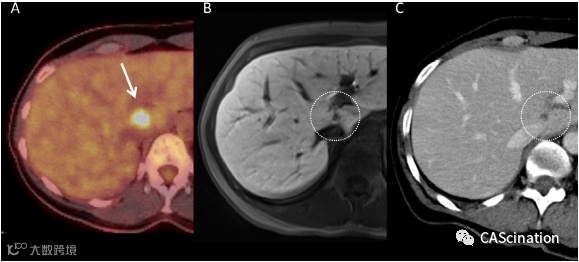

图 1 – FDG PET-CT(A,箭头),肝胆相中的MRI(用Gadoxetate (Primovist);B,点形圆)和静脉相中的对比增强CT(C,点形圆)显示尾状叶转移,直接附于左门静脉和下腔静脉。

本报告中患者是前瞻性临床研究的一部分,旨在评估接受经皮SIMWA治疗肝转移(非结直肠癌转移)的短期临床结果。这项研究得到了当地伦理委员会的批准。2016年5月,我院提供一位52岁女性患者,在筛查乳房X光片上发现右乳房异常。活检显示有浸润性导管癌(雌激素受体60%,孕酮受体5%-20%,Ki67 25%,阳性)。随后的FDG PET-CT显示肝脏尾状叶有活动性损伤。最后的肿瘤阶段是 T2, N0, M1。接受曲妥珠单抗(赫赛汀)、珀特珠单抗(perjeta)和多西他赛(taxotere)共5个周期(主要副作用导致多西他赛剂量减少)的化疗,随后接受曲妥珠单抗和珀特珠单抗的系统治疗。接受曲妥珠单抗(赫赛汀)、珀特珠单抗(perjeta)和多西他赛(taxotere)共5个周期(主要副作用导致多西他赛剂量减少)的化疗,随后接受曲妥珠单抗和珀特珠单抗的系统治疗。化疗开始后4个月,FDG-PET-CT显示肝转移活性降低(图1a)。右乳房手术(节段切除,肿瘤边缘阴性)1个月后辅以高剂量近距离放射治疗(累积剂量32(Gy))。

由于尾叶位置不利(图1),距下腔静脉仅4 mm,距左门静脉3 mm。因此,考虑到患者的肿瘤情况,跨学科肿瘤委员会推荐CT下SIMWA治疗。